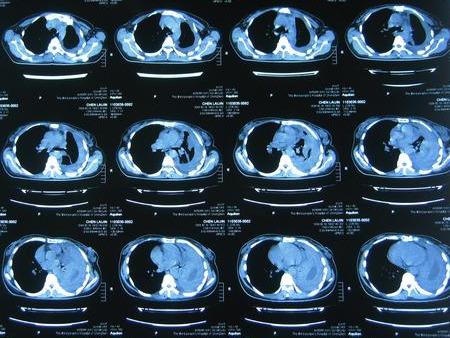

术后1年随访胸部CT:右肺膨胀良好,胸腔畸形纠正

术后1年胸片显示左侧脓胸及血型播散性肺结核已治愈